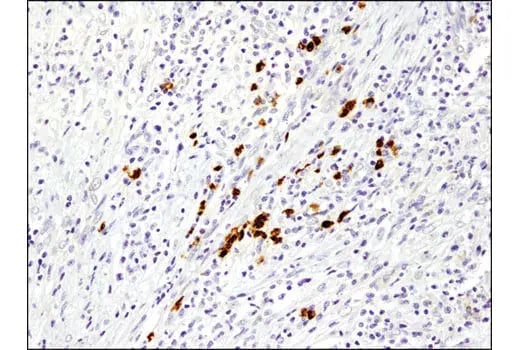

As tumor cells enter and travel through the bloodstream, they remain closely linked to an immunosuppressive microenvironment that helps them evade immune detection and clearance. Tumor cells and CAFs secrete factors such as CSF (G‑CSF), MCP‑1 (CCL2), IL‑6, IL‑1β, and CXCL12 (SDF1) to recruit myeloid‑derived suppressor cells (MDSCs) and tumor‑promoting M2 macrophages, often marked by CD163 and CD206.

MDSCs and M2 macrophages release immunosuppressive mediators, including Arginase‑1, IL‑10, and PD‑L1, which dampen cytotoxic T cell responses and protect associated tumor aggregates during intravasation and circulation. This immunosuppressive population functions as a mobile shield that accompanies clusters of circulating tumor cells, increasing their chances of surviving immune attack in the bloodstream.

![]() |

| IHC analysis of paraffin-embedded human colon adenocarcinoma using Arginase-1 (D4E3M™) Rabbit Monoclonal Antibody #93668 performed on the Leica BOND RX. | IHC analysis of paraffin-embedded human non-small cell lung carcinoma using PD-L1 (E1L3N®) Rabbit Monoclonal Antibody #13684 performed on the Leica BOND RX. |